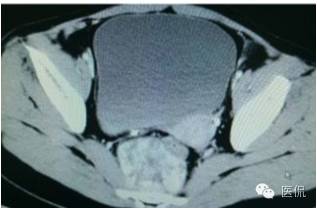

女,37岁,体检超声发现盆腔包块一周。无其他异常。

CT平扫(CT值23HU)